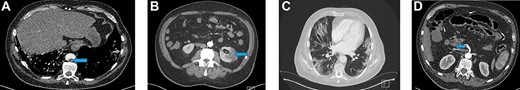

Blood investigations showed an elevated white blood cell count (WCC), a low lymphocyte count and elevated C-reactive protein (CRP). The thrombin time was prolonged (Table 1). A computed tomography (CT)—angiogram of lower limbs showed complete thrombosis of the infrarenal aorta, the common and external iliac arteries bilaterally, the left common, proximal superficial and profunda femoral arteries (Fig. 1A). A CT scan of the chest showed patchy and ground-glass shadowing predominantly in the bilateral lower lung lobes (Fig. 1B). A throat swab was positive for COVID-19.

(A) A CT scan of the chest showed patchy and ground-glass shadowing predominantly in the bilateral lower lung lobes. (B) CT-thorax showing pulmonary changes. (C) CT-angiogram demonstrating aorta and left CIA patency with residual thrombus in right CIA post-operatively (blue arrow)